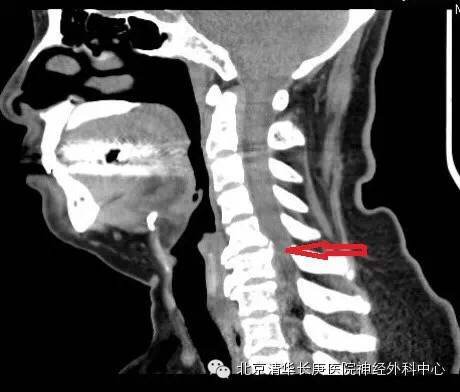

CT显示:C5-6,6-7椎间盘突出,后纵韧带骨化

术中O-ARM及导航联合精准定位及内固定

术中、后O-ARM确定:C5-6前路板固定良好